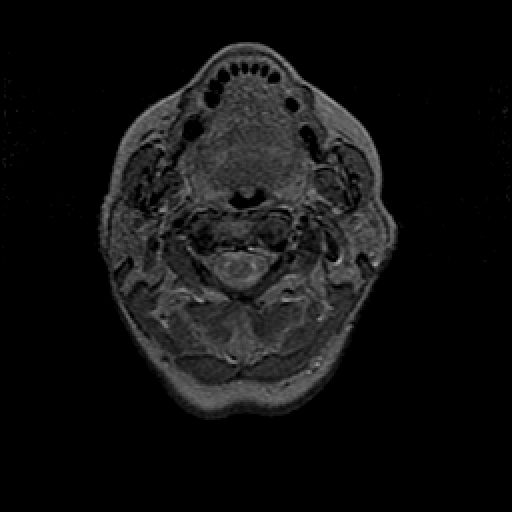

Proton density-weighted structural MR: Slice 0

Slice 0